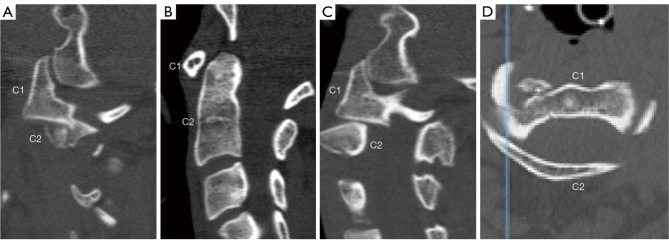

Atlantoaxial rotatory subluxation (AARS) in the adult population is primarily trauma-induced. Conservative and surgical treatments have both been used successfully in treating AARS. In cases where AARS cannot be reduced by conservative measures, open reduction and fusion is the conventional treatment approach. This report details a novel approach for treating adult AARS, where an open reduction was performed without instrumentation or fusion. The patient, a 48-year-old female involved in a high-speed vehicular collision, initially underwent conservative treatment with Gardner Wells Tongs and manual traction. Despite these efforts, X-ray and computed tomography (CT) scans indicated persistent subluxation. Subsequently, the patient was taken to the operating room, where successful open reduction was achieved without the need for fusion or instrumentation. Preoperative imaging revealed rotatory subluxation of C1-2 with a comminuted and displaced fracture of the right C1-2 facet joint and a nondisplaced fracture of the base of the occiput. The surgical technique involved precise manual manipulation using a Cloward spreader and real-time assessment with O-arm 3D X-ray tomography to ensure successful reduction. The absence of significant laxity or instability during intraoperative testing led to the conclusion that fusion was unnecessary. This approach minimizes invasive tissue dissection and preserves natural cervical range of motion (ROM). Postoperatively, the patient was asymptomatic with no joint instability and demonstrated satisfactory alignment at follow-up.